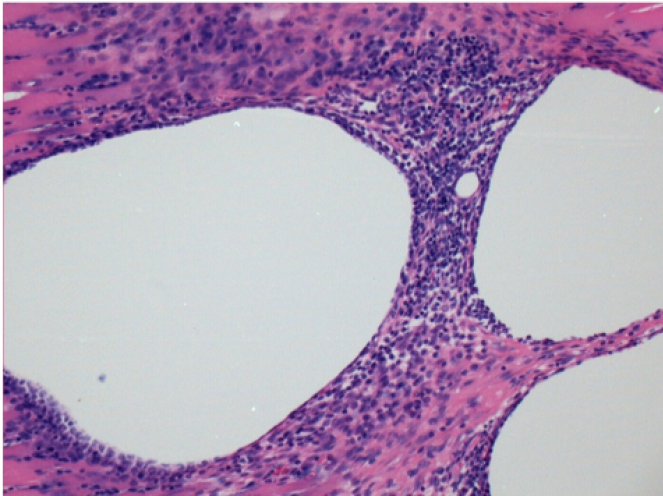

10 giorni dopo iniezione di Endopeel

Scatola Nr 2

- 10 giorni dopo iniezione 0.1ml di Endopeel nel muscolo pretibiale destro (Dx).

- Si osserva formazioni di vacuole , le quali circondate da linfociti.

- Le quali Vacuole sono differenti dal tessuto necrotico.

- La presenza di linfociti é correlata alla permeabilità delle membrane cellulari.

Dx :400x - Giorno10